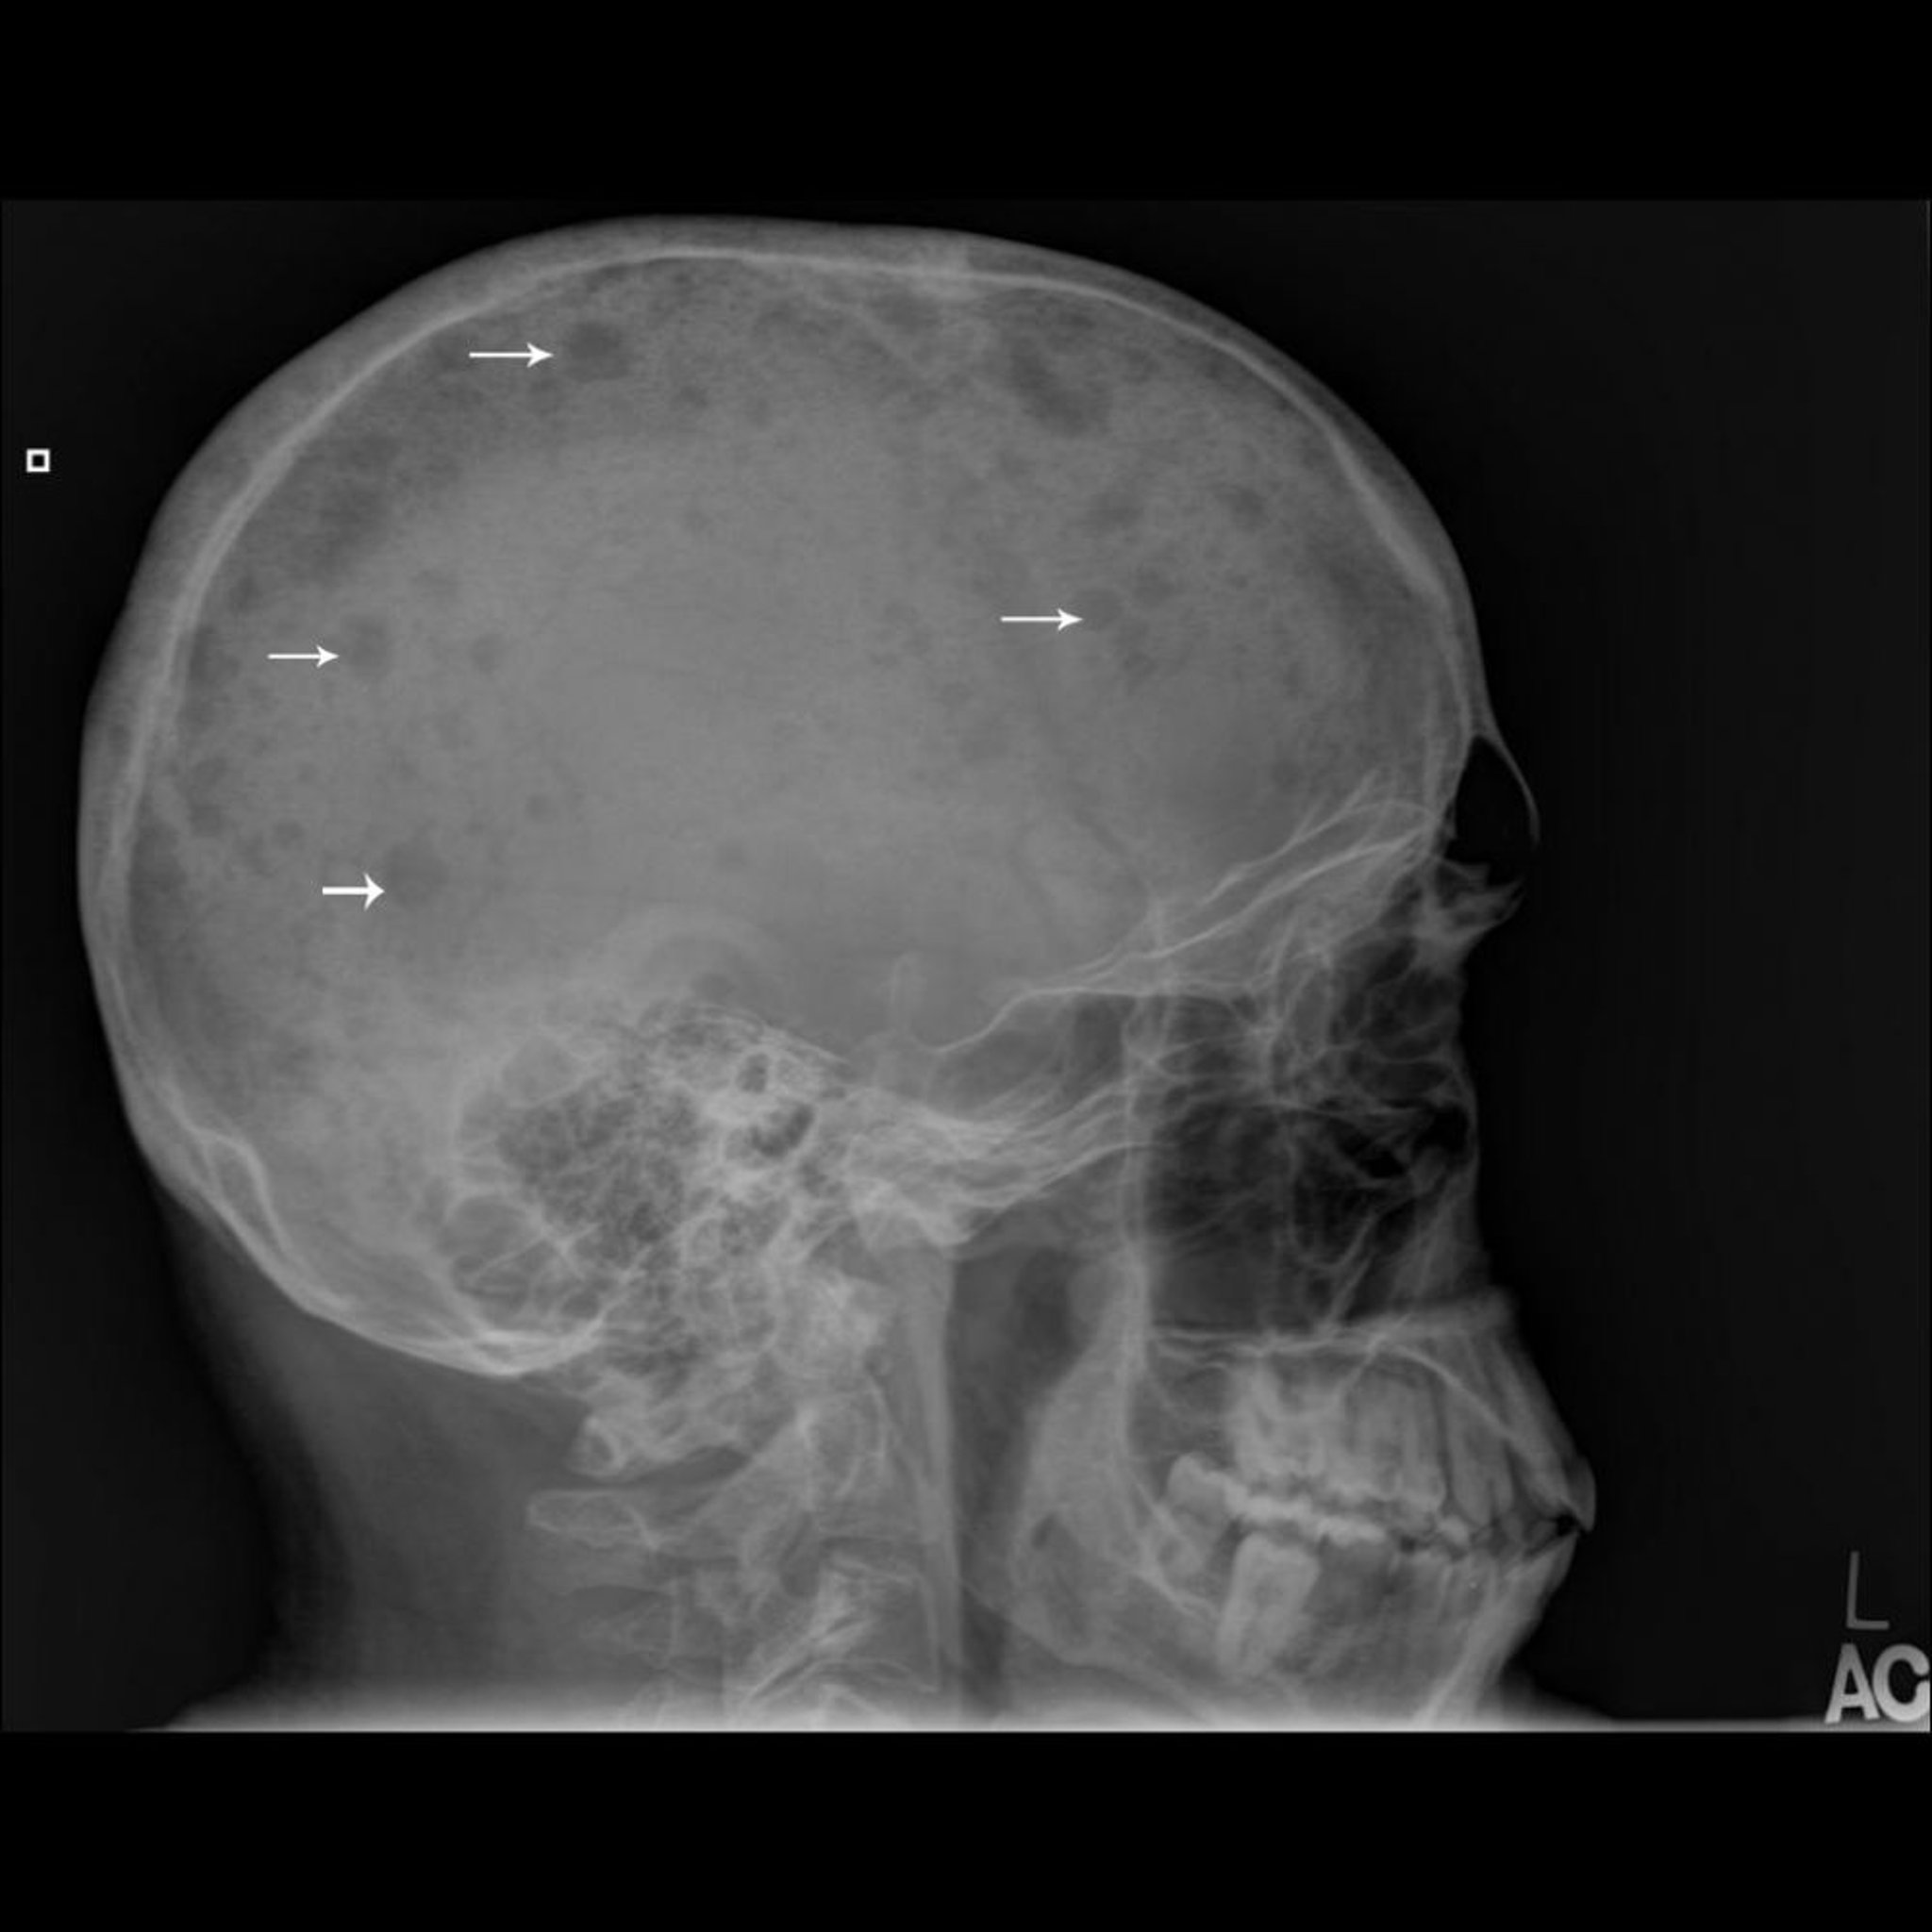

Radiografia cranica che mostra numerose aree in rilievo sull’osso (frecce) tipiche del mieloma multiplo.

Per gentile concessione di Michael J. Joyce, MD e Hakan Ilaslan, MD.